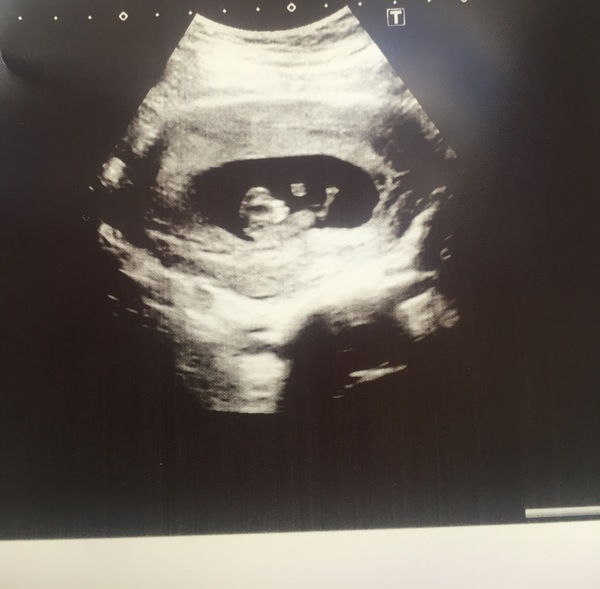

Hi everyone! Haven't caught up since the last thread, so hi to all the newbies! I had some severe cramping yesterday (9+4 today) spoke to the GP who sent me for an early scan to rule out ectopic. I went today & saw baby, all is well Smile unsure what caused the pain but it has stopped now, cervix closed, baby in the right place & a strong heart beat. Picture - I'm surprised how grown baby looks already! Give some of you ladies an idea of what they look like at this stage if you haven't had a scan yet Smile